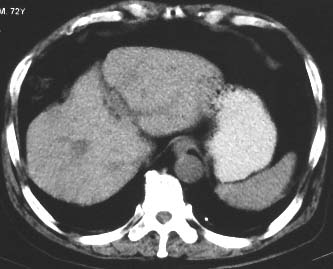

男 56 腹部不舒

典型肝硬化:1、肝各叶大小的比例失常;2、肝表面明显凹凸不整,边缘变钝;3、肝实质密度一般与正常肝无明显改变;4、肝裂增宽;5、门静脉增宽,脾静脉扩张扭曲;6、脾脏虽然不大,但不是所以肝硬化的脾脏都增大。

典型肝硬化:1、肝各叶大小的比例失常;2、肝表面明显凹凸不整,边缘变钝;3、肝实质密度一般与正常肝无明显改变,但肝右叶似可见再生结节影;4、肝裂增宽;5、门静脉增宽,脾静脉扩张扭曲;6、脾脏增大. 脾脏大小的标准有:1脾脏的左右径(大于5个肋单元) 2脾脏的宽度 3脾脏的上下径(超过肝下缘) 请参考.

典型肝硬化:1、肝各叶大小的比例失常;2、肝表面明显凹凸不整,边缘变钝;3、肝实质密度一般与正常肝无明显改变,但肝右叶似可见再生结节影;4、肝裂增宽;5、门静脉增宽,脾静脉扩张扭曲;6、脾脏增大.

典型肝硬化:1、肝各叶大小的比例失常;2、肝表面明显凹凸不整,边缘变钝;3、肝实质密度一般与正常肝无明显改变,但肉眼观察与脾胀密度低或等密度;4、肝裂增宽;5、门静脉增宽,脾静脉扩张扭曲;6、脾脏增大.

典型肝硬化:1、肝各叶大小的比例失常;2、肝表面明显凹凸不整,边缘变钝;3、肝实质密度一般与正常肝无明显改变,4、肝裂增宽;5、门静脉增宽,脾静脉扩张扭曲;6、脾脏增大.

肝硬化表现符合,肝脾ct值有倒置,考虑局灶性肝脂肪浸润